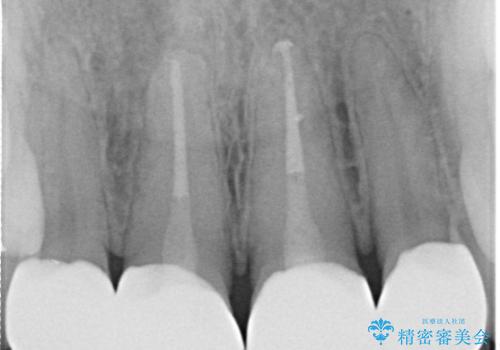

- 「前歯の色が気になる」を主訴に来院された患者様です。前歯が咬んでない開咬という状態のため、矯正治療を勧めましたが、患者様がご希望されなかったためオールセラミッククラウンで治療を行いました。右上1番は、神経の検査の結果、神経が死んでいたため根管療から行いました。左上1番は、金属の土台が入っていたのとラバーダムシートを使用せず根管治療が行われていたため、再度根管治療から行いました。その後ファイバーコアをたてオールセラミッククラウンで治療を行いました。

※根管治療では根管内に細菌を入れない事がとても大切なので必ずラバーダムシートとマイクロスコープを使用して根管治療を行っています。